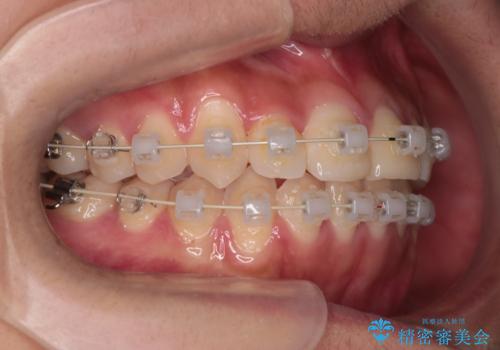

- 矯正装置

- 審美装置

- 治療期間

- 1年6ヶ月

装着時間に不安がある人は、ワイヤー矯正をおすすめしております。短期間で治療でき患者様にも満足していただきました。